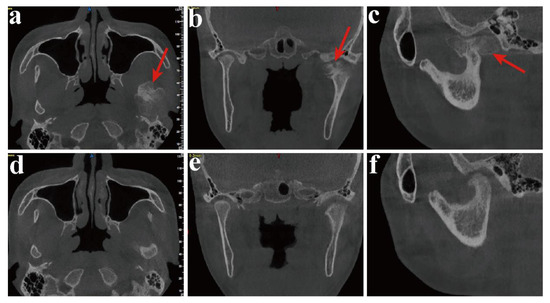

3.1. Evaluation of Clinical Features

3.2. Evaluation of the Accuracy of Condylar Osteotomy with DOS and DOT